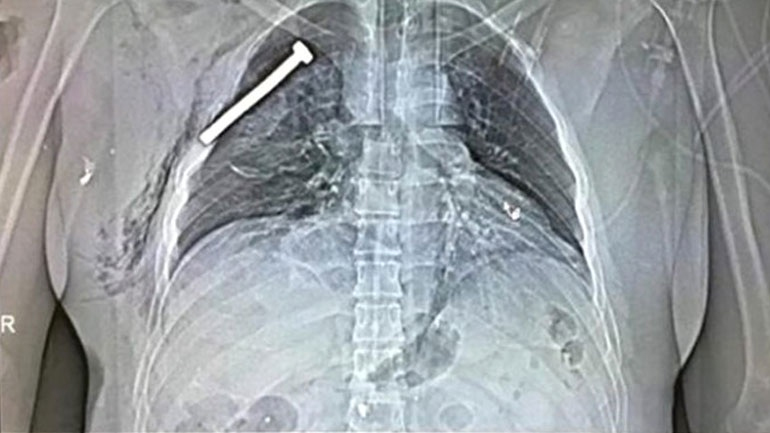

Την ίδια ώρα συγκλονίζει η φωτογραφία που έδωσε στη δημοσιότητα η γαλλική εφημερίδα «Le Soir», στον απόηχο των πολλαπλών «χτυπημάτων» στην καρδιά της Ευρώπης.

Πρόκειται για μία ακτινογραφία ενός εκ των θυμάτων, στην οποία φαίνεται ξεκάθαρα ότι έχει καρφωθεί μια… βίδα στον θώρακά του. Σύμφωνα με τον τελευταίο επίσημο απολογισμό, 31 άνθρωποι έχασαν τη ζωή τους.

Όπως μετέδωσε το ABC, οι ζώνες με τα εκρηκτικά που φορούσαν οι βομβιστές αυτοκτονίας φέρεται να είχαν ενσωματωμένα καρφιά και πρόκες προκειμένου να προκαλέσουν ακόμα μεγαλύτερη ζημιά.